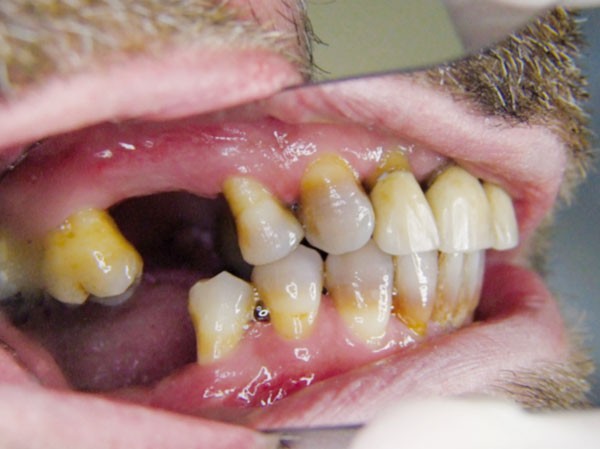

L’examen clinique du patient en consultation d’implantologie débutera donc par un examen visuel du site et se poursuivra par une palpation de la région (fig. 1).

La largeur de la crête sera alors estimée mais seule l’analyse d’un cliché radiographique en 3D de type Cone Beam (CBCT) sera à même de préciser le volume osseux disponible. En cas d’insuffisance, de volume osseux vertical une élévation de sinus pourra être proposée (fig. 2).